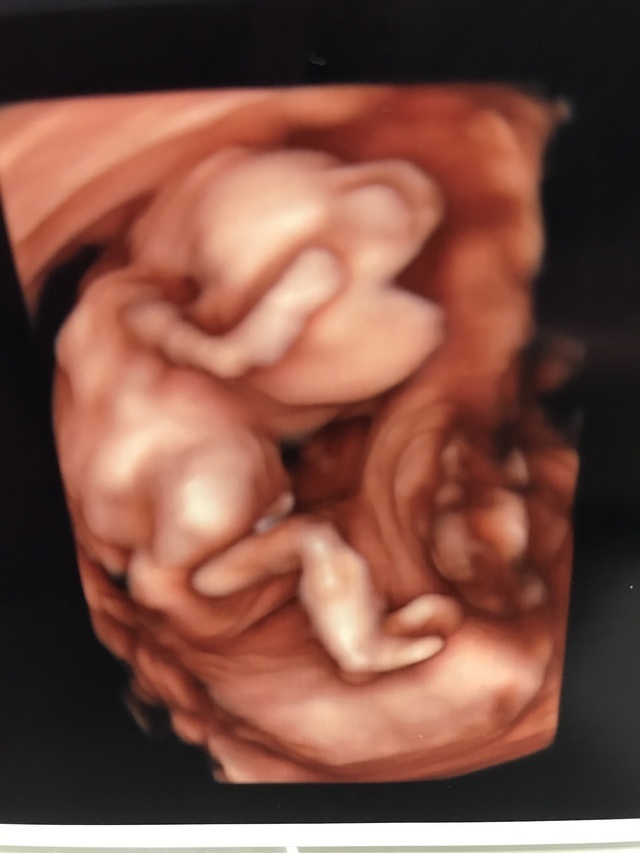

15週3日(15w3d・男の子)|kaaaa さん(25歳)

エコー写真撮影時のエピソード:

第二子にして初めて4Dエコーを貰った時のものです。まだ4ヶ月で胎動もなく今まで3Dエコーではぼんやりとした輪郭しか分からなかったのにちゃんと人の形になってる!!と感動しました。

主人も今まではエコーを見ても「ふーん」ぐらいの素っ気ない返事でしたが、これには喜んでくれました!やっぱり見やすい方が実感湧くのでしょうか。(笑)

上の子もまだ1歳でしたが、この頃から「ママのお腹には赤ちゃんがいるんだよ~~。こんなして寝んねしてるよ~~。」と話していました。毎日お腹をさすってくれて産まれる前からお姉ちゃんをしてくれています。